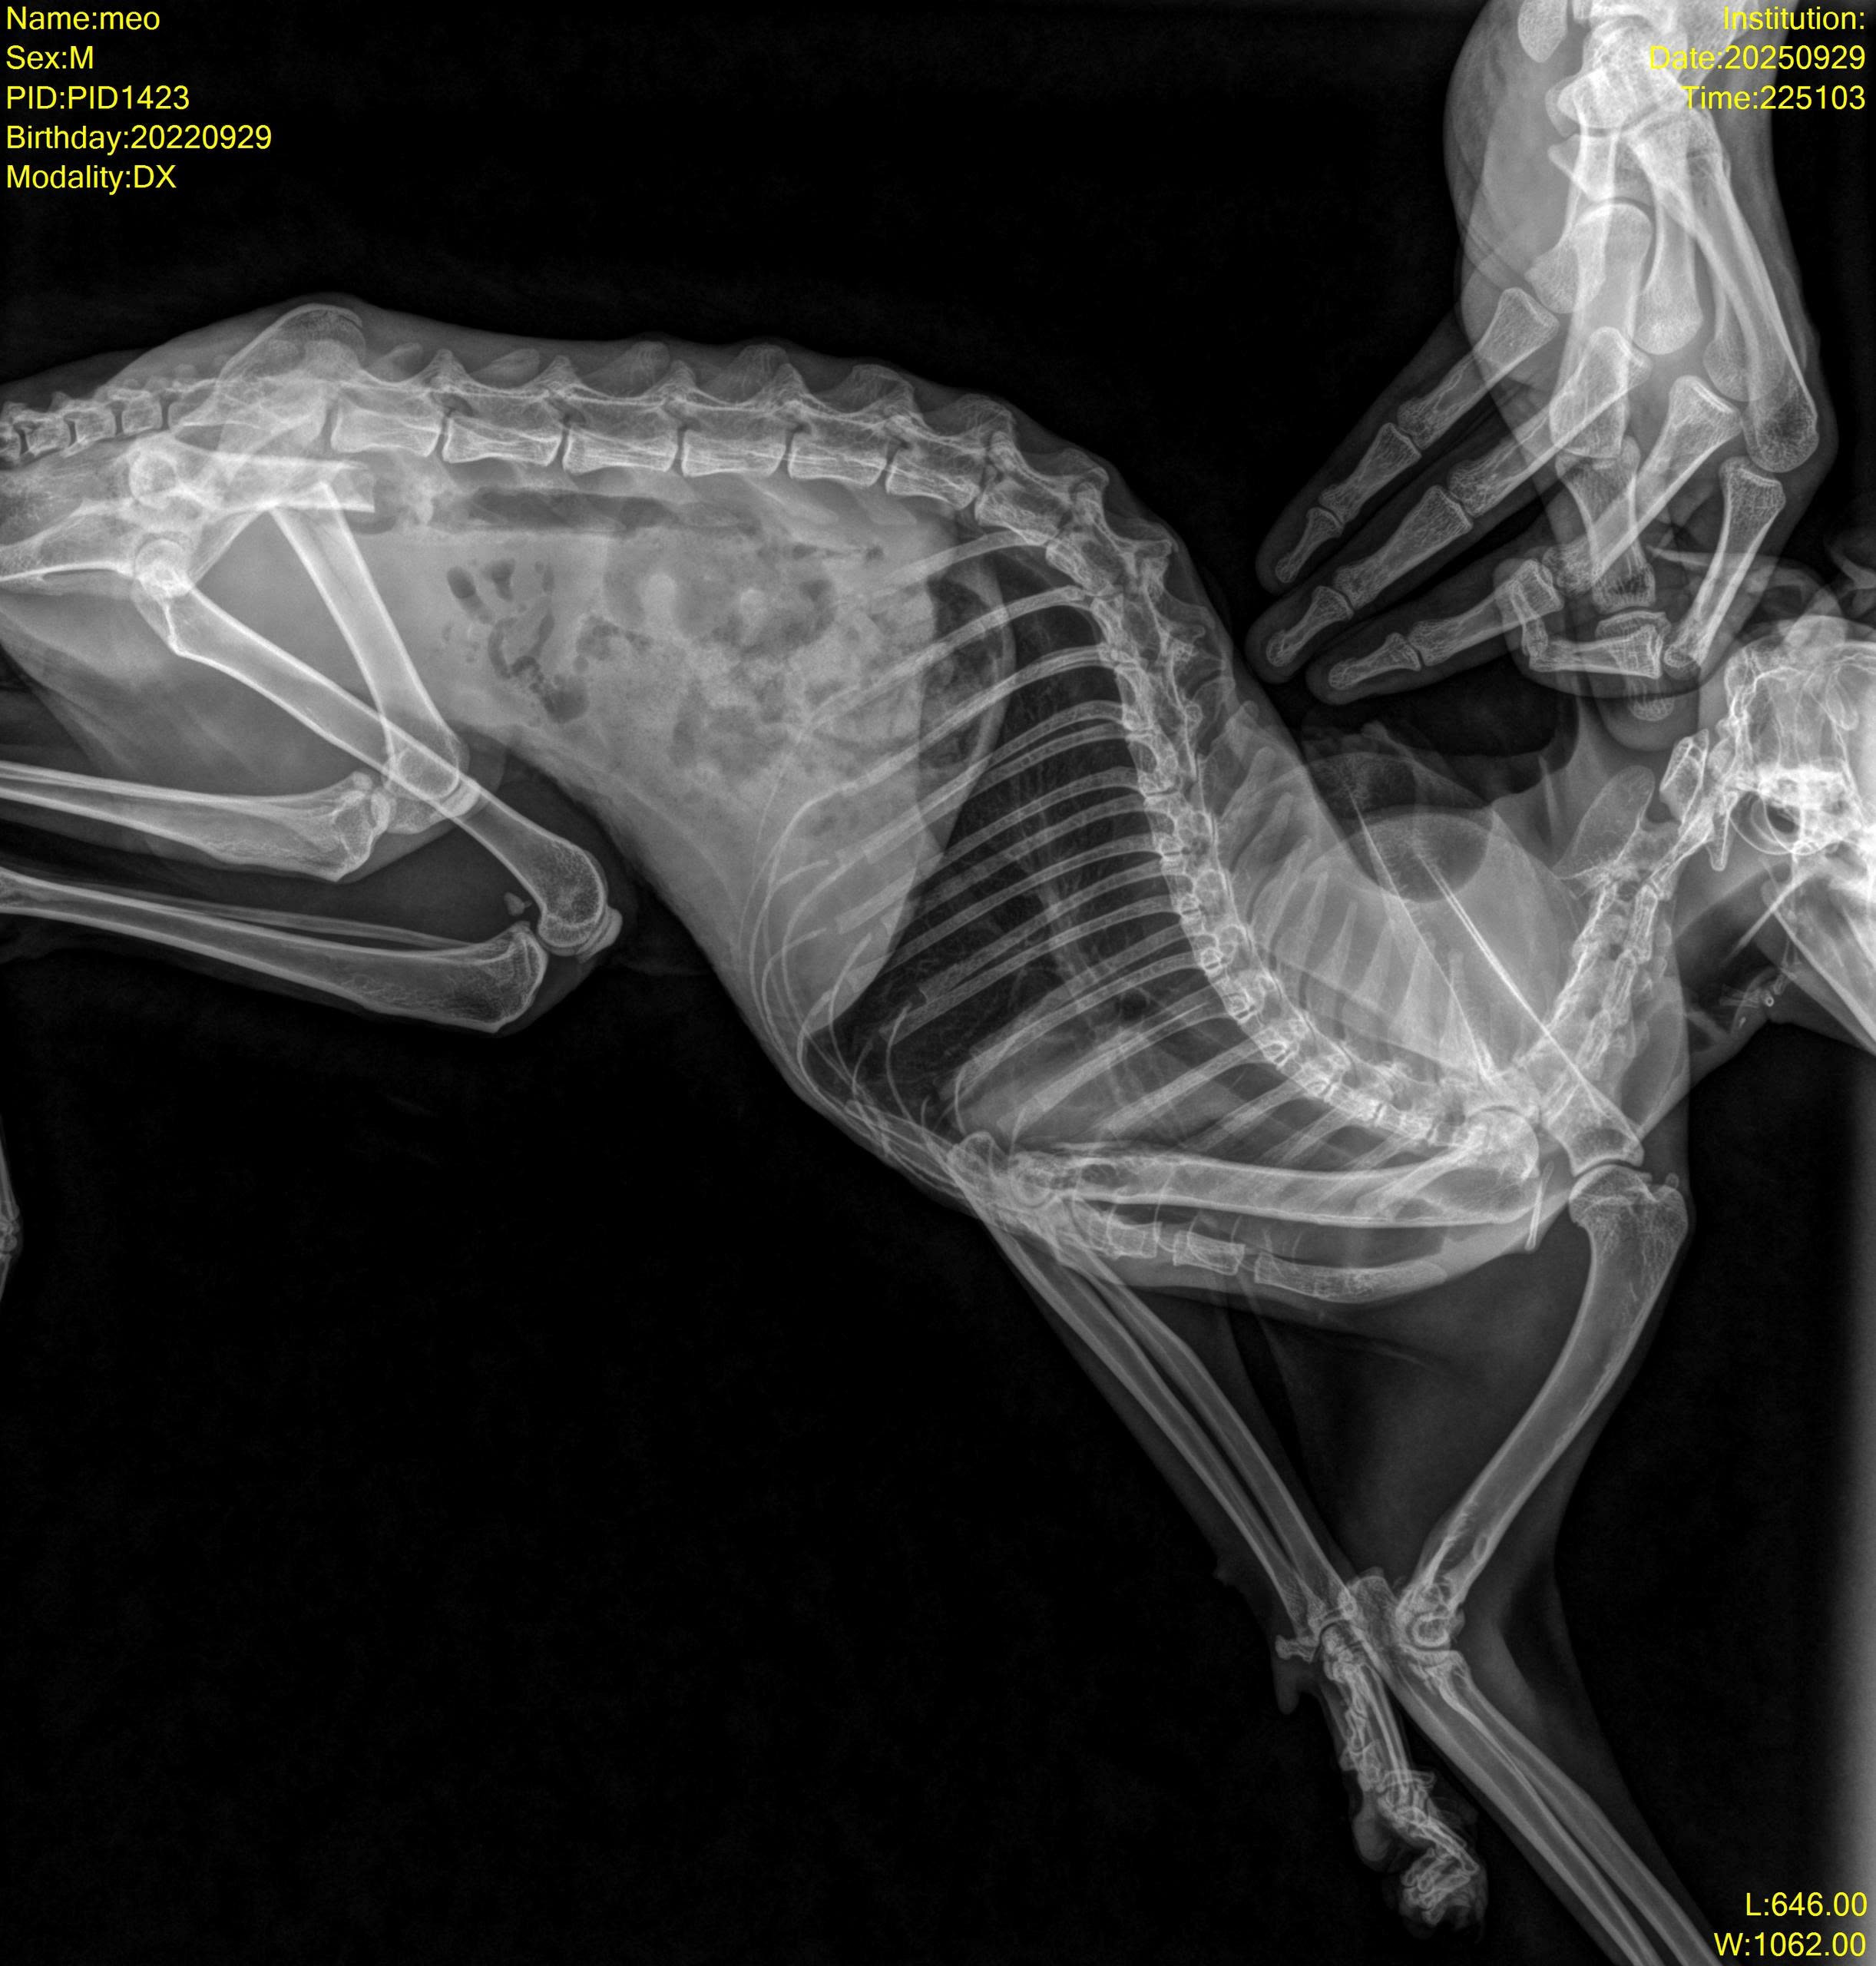

Một bạn nhặt được bé ngoài đường Mèo đực đã thiến, thể trạng gầy gò, mất nước. Niêm mạc nhợt nhạt, hai chân sau yếu, cham vào sẽ kêu đau. Trên người có vết cạo xước mất lông